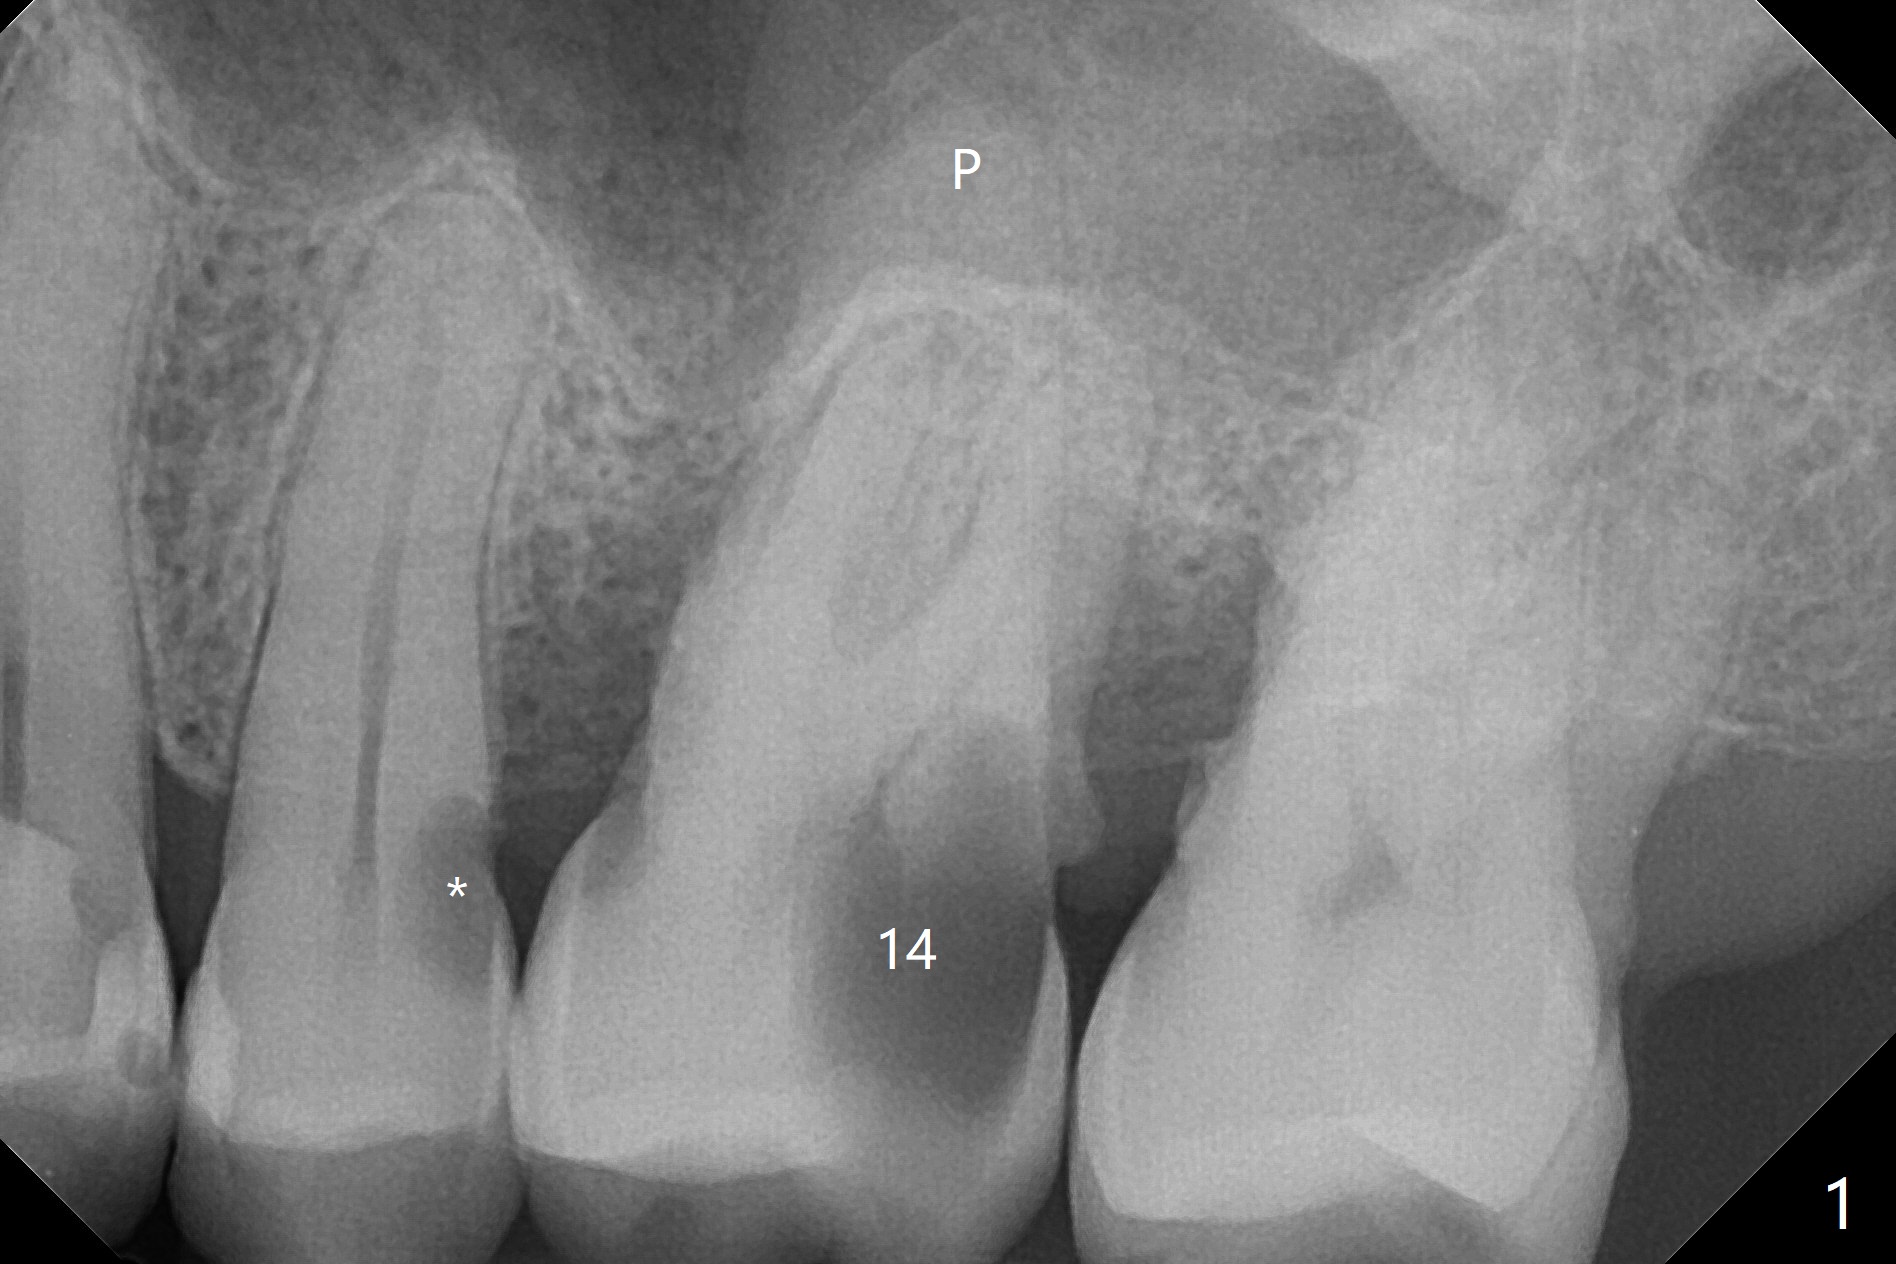

72岁男14号牙腭侧根尖接近上颌窦(图一,二:P),牙齿拔除后,根尖对刮治敏感,冲洗后,开始导板钻洞,圆钻穿透窦底,放置粘性骨粉和报废植体提升(图三:箭头)。放置小张PRF和骨粉(图四:箭头),植入正式植体,基台和骨粉(图五:*),最后覆盖PRF(图六),为了防止骨粉从邻牙牙龈沟(>)丢失,覆盖树脂敷料。基台和前后邻牙使树脂敷料术后一周巍然不动(图七:A)。术后一个月撤除树脂敷料,牙槽窝已经愈合(图八)。再过两周牙槽窝上皮好像进一步成熟(图九),然后塞入一个龈线,制备临时牙冠。